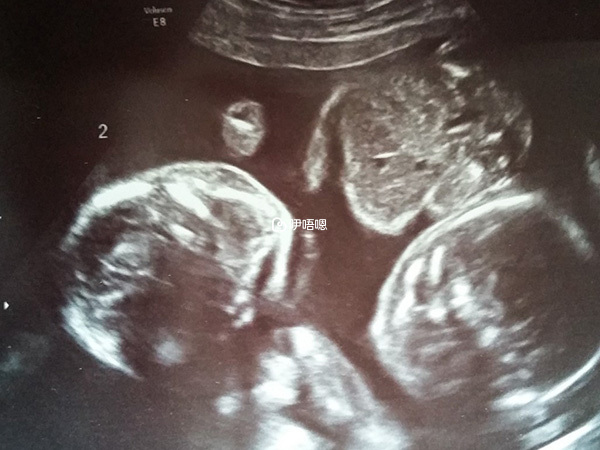

我當時又在圈子裡發求助,找姐妹邦的姐妹給我確認了一下,確確實實是雙槓,當時眼淚又掉了,這次是幸福的眼淚,終於等到抽血的那天,13天,凍胚,血值1144,當時那個激動呀,這下終於懷上了,現在B超回來,我是雙胎媽媽,上天終於眷顧我這個可憐的小女子!